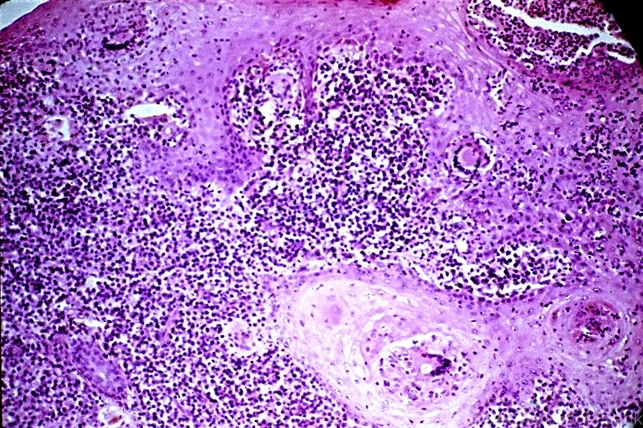

- acanthosis, fungal ulcer

- Marked downward proliferation of acanthotic epithelium (pseudoepitheliomatous hyperplasia) at the edge of a fungal ulcer.